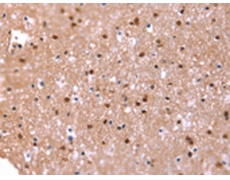

IHC positive control: |

Human brain |

IHC Recommend dilution: |

25-100 |